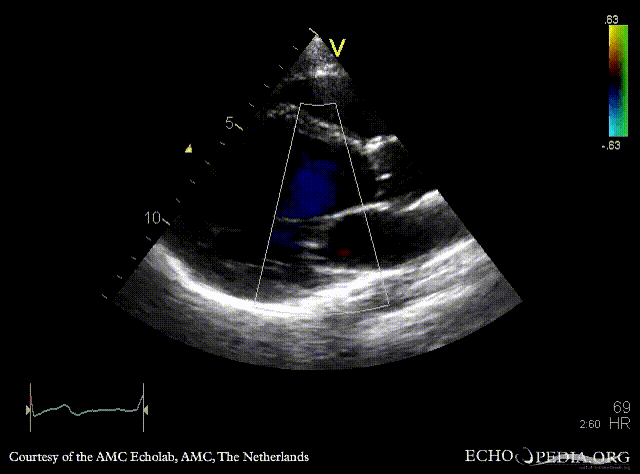

Dilated cardiomyopathy

PLAX: Color Doppler, moderate mitral regurgitation A4CH: dilated poor left ventricle